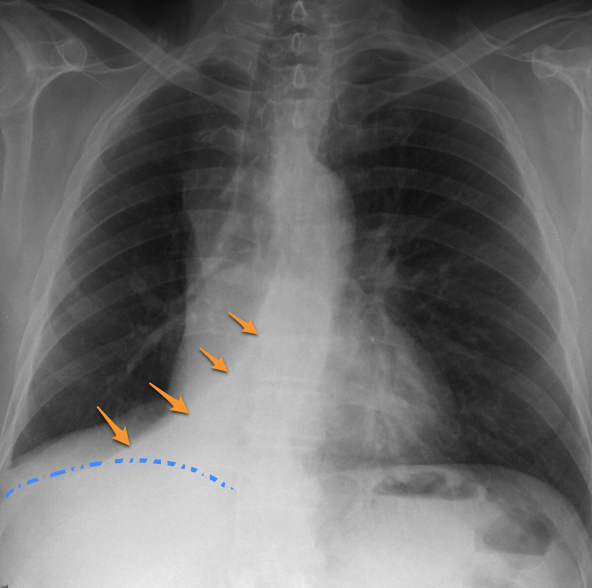

Round Atelectasis

Focal atelectasis with a round morphology that is always associated with an adjacent pleural abnormality (e.g. pleural effusion, pleural thickening or plaque, pleural neoplasm, etc). Round atelectasis is most common in the posterior lower lobes. All five of the following findings must be resent to diagnose round atelectasis: 1. Adjacent pleura must be abnormal. 2. Opacity must be peripheral and in contact with the pleura. 3. Opacity must be round or elliptical. 4. Volume loss must be present in the affected lobe. 5. Pulmonary vessels and bronchi leading into the opacity must be curved, this is the comet tail sign.